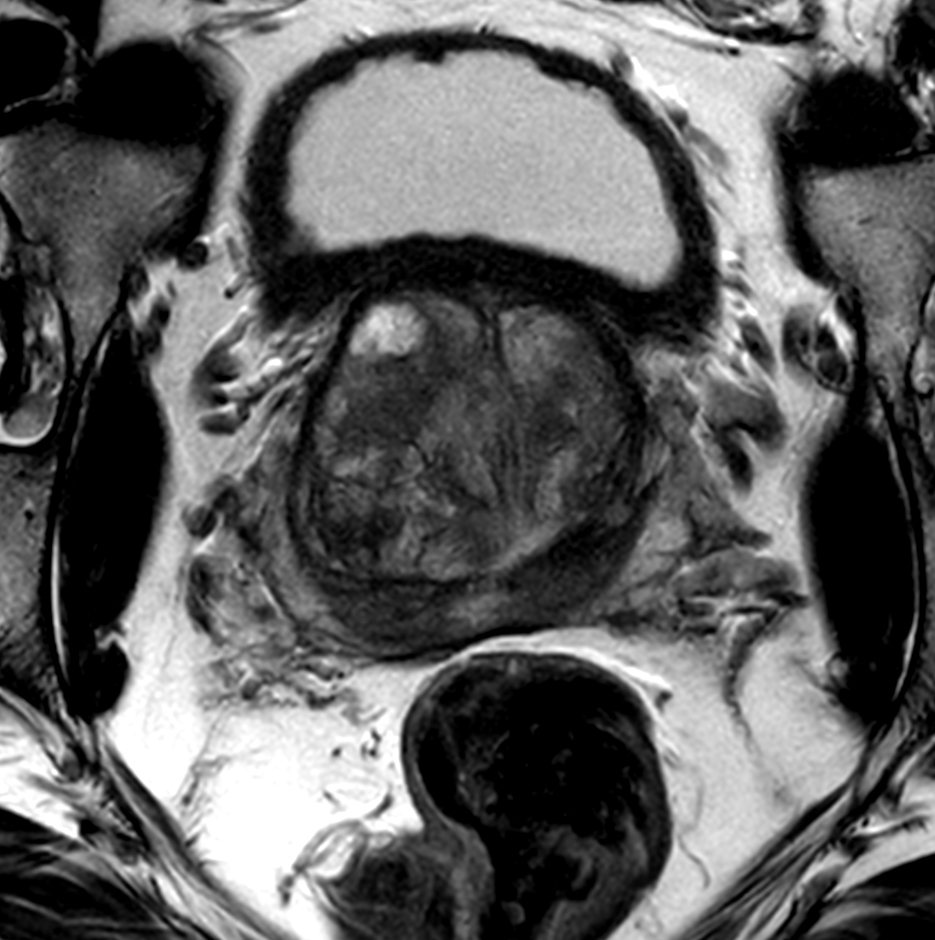

Axial T2w TSE